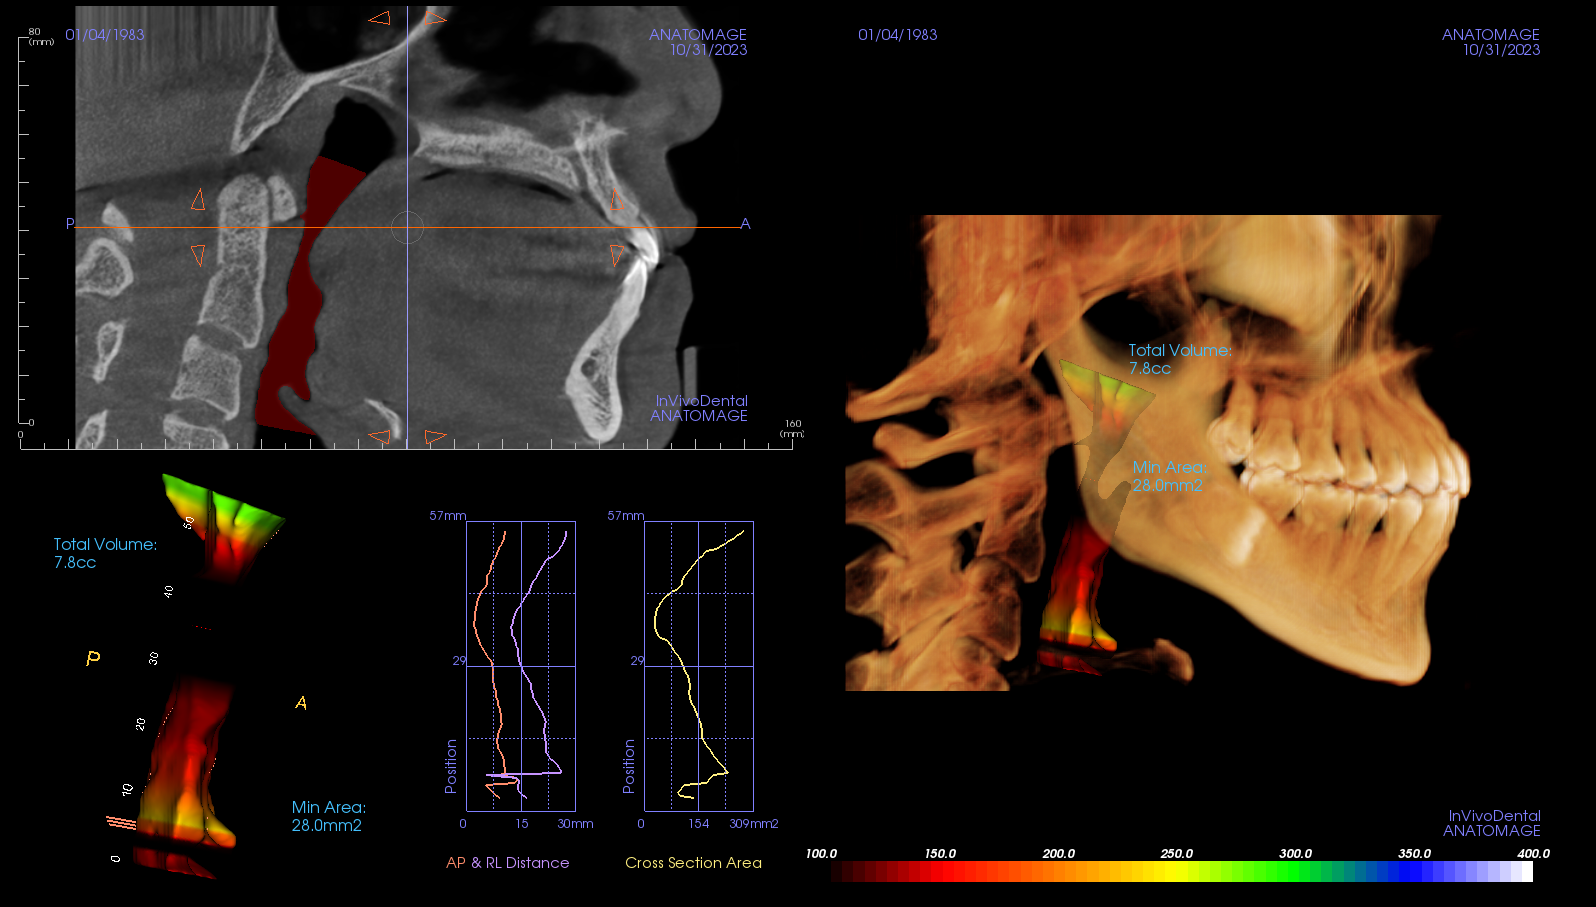

- 呼吸道電腦斷層:現在可以透過電腦斷層評估你的呼吸道空間,確認呼吸道結構是否狹窄、阻塞,幫助醫師判斷是否需要進一步處理呼吸道問題。

後來,楊先生來到丰采美學牙醫的睡眠特別診所進行進一步評估。診所的醫師發現,楊先生的下巴明顯後縮,結構性問題導致他的呼吸道空間受限。再加上他長期以來習慣用口呼吸,使得舌頭和口腔肌肉的支撐力不足,進一步加劇了睡眠期間的呼吸道塌陷,導致呼吸阻礙。醫師解釋,楊先生的情況是典型的『結構性』睡眠障礙,需要透過專業的結構性治療和功能性訓練來改善。